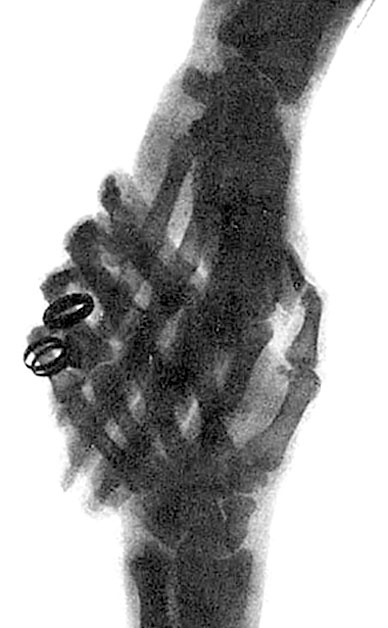

Рука, сфотографированная лучами Рентгена

Это тоже один из первых снимков, сделанных Рентгеном. Рука на фотографии – жены Рентгена. Видно кольцо, надетое на палец.